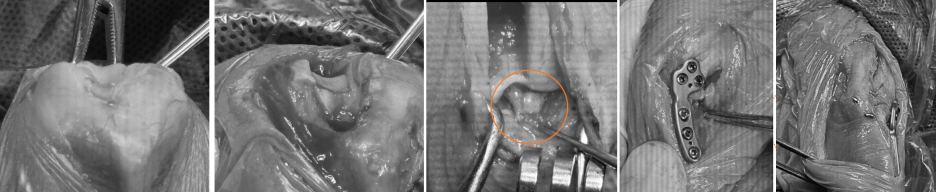

■ 슬개골 탈구 교정 수술

✔️활차구 성형술: 슬개골이 이탈하지 않도록 무릎 고랑을 더 깊게 만들어줌

✔️경골조면 이동술: 슬개골이 정상 위치에서 안정적으로 움직일 수 있도록 이동

■ 십자인대 파열 수술

✔️ TPLO 수술

종아리뼈를 절골한 후 TPLO플레이트를 장착하여 무릎관절의 안정성을 확보하는 수술 방법입니다.

(1) 수술 전 낮은 활차구 고랑 (2) 수술 후 깊어진 활차구 고랑 (3) 육안으로 확인된 십자인대 파열 (4) 절골 후 TPLO 플레이트 장착 및 경골조면 이동술 / 출처: 에스동물메디컬센터

에스동물메디컬센터는 최소 절개, 무릎 안쪽 절개로 추후 피부 유합 후에도 흉터가 적도록 세심하게 수술을 진행합니다.

환자는 총 60 여분의 슬개골탈구 수술 + TPLO 동시 교정 수술을 마치고 안전하게 마취에서 깨어나 회복하였습니다.